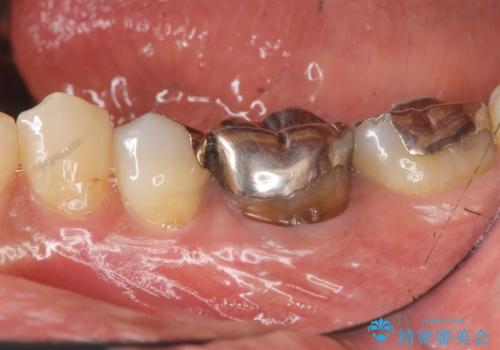

目立つ銀歯を白くしたい

- 「笑った時に目立つ銀歯をきれいにしたい、皮膚科で金属アレルギーの可能性を指摘されたので金属を外したい。」

、とセラミック治療を希望され来院されました。

残っている歯を削らないよう、丁寧に除去したのち精密なジルコニアセラミッククラウンで再咬合構成を行っていきます。

見た目の改善が達成できたとともに、皮膚のかゆみも明らかに減少したと喜んでいただくことができました。